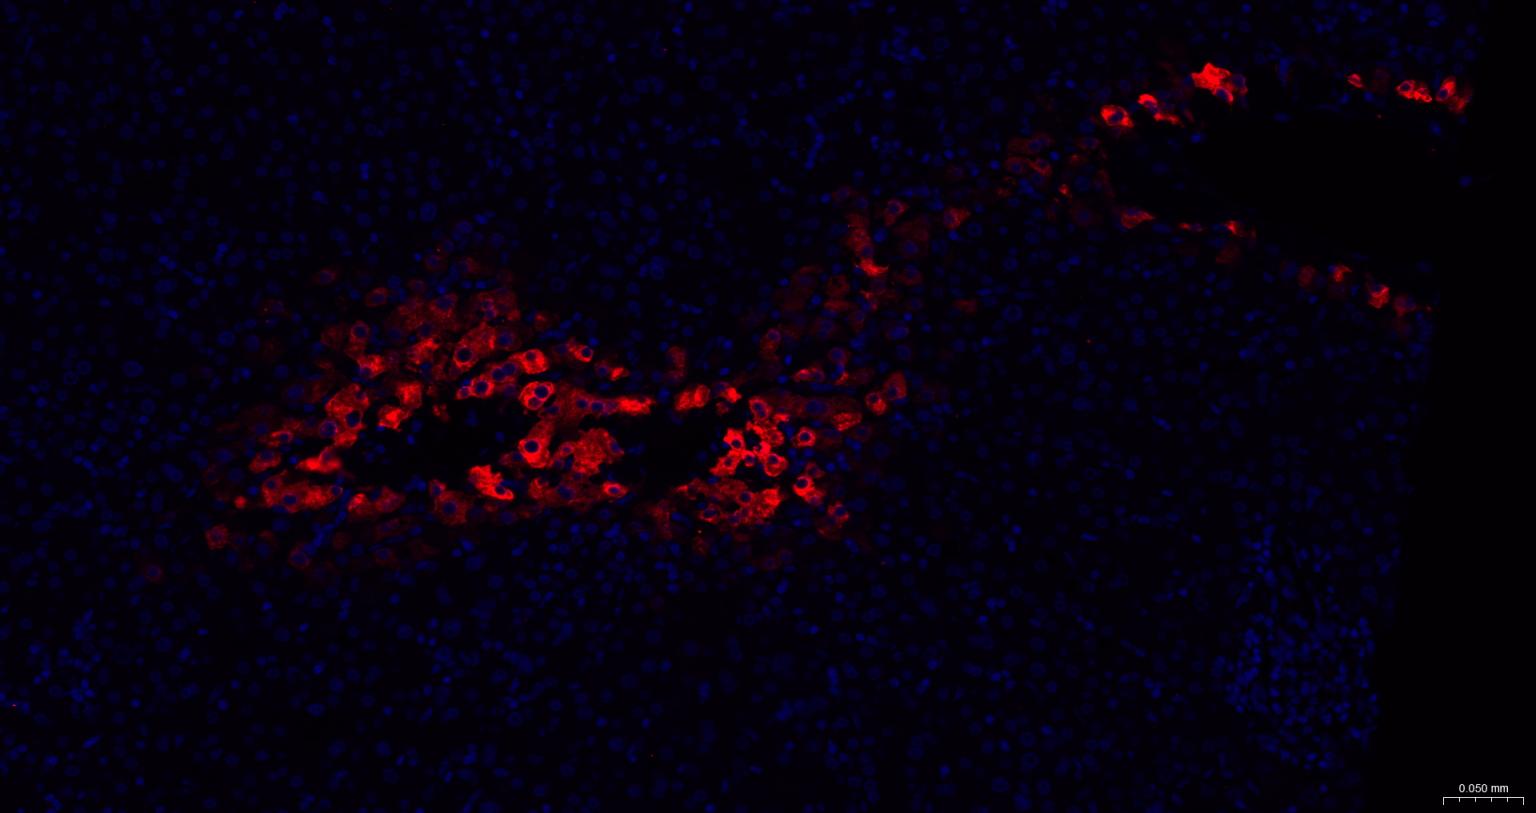

Paraformaldehyde-fixed, paraffin embedded Human Liver; Antigen retrieval by boiling in sodium citrate buffer (pH6.0) for 15 min; The section was incubated with Glutamine synthetase Polyclonal Antibody, Unconjugated (bs-42310R) at 1:200 overnight at 4°C. Followed by conjugated Goat Anti-Rabbit IgG antibody (Red, bs-0295G-BF594), DAPI (blue, C02-04002) was used to stain the cell nuclei.

Paraformaldehyde-fixed, paraffin embedded Mouse Liver; Antigen retrieval by boiling in sodium citrate buffer (pH6.0) for 15 min; The section was incubated with Glutamine synthetase Polyclonal Antibody, Unconjugated (bs-42310R) at 1:200 overnight at 4°C. Followed by conjugated Goat Anti-Rabbit IgG antibody (Red, bs-0295G-BF594), DAPI (blue, C02-04002) was used to stain the cell nuclei.

Paraformaldehyde-fixed, paraffin embedded Rat Liver; Antigen retrieval by boiling in sodium citrate buffer (pH6.0) for 15 min; The section was incubated with Glutamine synthetase Polyclonal Antibody, Unconjugated (bs-42310R) at 1:200 overnight at 4°C. Followed by conjugated Goat Anti-Rabbit IgG antibody (Red, bs-0295G-BF594), DAPI (blue, C02-04002) was used to stain the cell nuclei.